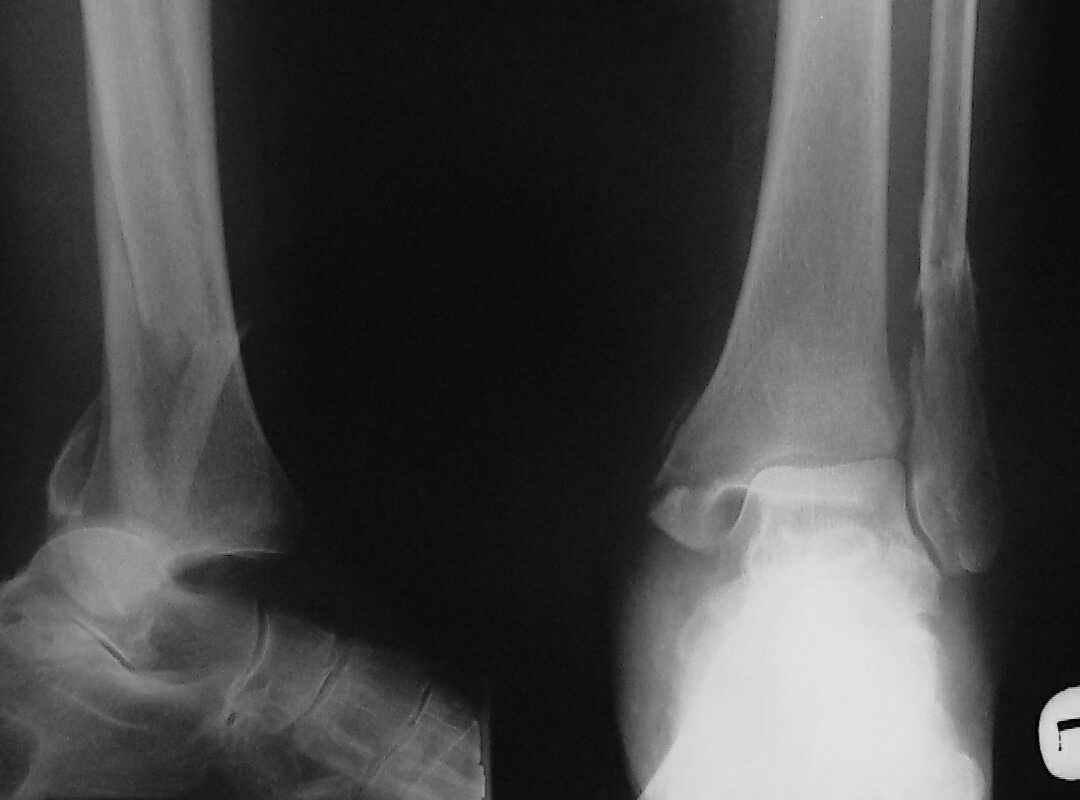

При поступлении - закрытая репозиция, повторная в связи с большим отеком через неделю, подготовлена к остеосинтезу в первых числах декабря. Заживление без осложнений. Циркулярный гипс - 7 недель, снят,часть спиц удалено 20 февраля т.к.пальпировались под кожей, постепенная нагрузка, проблем нет до середины апреля когда появильсь боли с мед. стороны сустава и локалная гиперемия ( трактовалась как флеботромбоз). Повторное поступление 15 апреля - усиление болей,пов. температура, локально выраженная гиперемия.Локально выделений нет. На RTG - деструкция в области мед лодыжки и заднего края. Сахар крови умеренно повышен. Как трактовать проблему, какой диагноз и тактика лечения? Заранее спасибо, Владимир.

Диагноз я бы поставил: неправильно срастающийся перелом обеих лодыжек и заднего края ББК. Ложный сустав мед. лодыжки? Хронический вялотекущий остеоимиелит голеностопа. Сопутствующий - СД, диабетическая ангиопатия 2.

Ретроспективно, на Ваш взгляд, что изменилось бы при остеосинтезе более массивными имплантами?(выбор в пользу спиц как раз и был из-за минимального объема оставляемых имплантов) Иммобилизация 7 недель это очень длительно? Результат на 4 RTG - в чем нефункциональность? - согласен, что репозиция заднего края не была достигнута. Какие признаки ложного сустава мед. лодыжки ?

Уважаемый Владимир. Нестабильность и нефункциональность, как мне видится по снимочкам, была изначально,об этом ниже В чём вы видите массивность третьтрубчатой, например титановой 1.5 мм пластины? Ими оперируют во всём мире и получают хорошие результаты, а почему у нас это массивно мне непонятно.Спицевая "тюрьма" хороший способ, но только для временной интраоперационной фиксации, хотя лично я редко пользуюсь, на то есть костодержатели для малых фрагментов и репонирующие винты. Кстати в данном случае, при её остеопорозе лучше было бы поставить LCP (опуская финансовую сторону вопроса, в теории). А вот функциональность - при правильном подборе и установке металлоконструкций пациент нуждается в иммобилизации на срок заживления швов, а уж потом ходьба без нагрузки на оперированную конечность 6 недель - (базовый курс АО). Ретроспективно, как мне видится, при хорошей репозиции и фиксации всё бы консолидировалось, хотя на всё воля божья, но по крайней мере не нужно было бы удалять железки. Иногда ставишь всё как мама родила, а потом очень плохие последствия. Признаки ложного (?) я вижу на снимках,хотя это может быть и банальное отсутствие консолидации за столь длительный срок, что само по себе я бы расценил как ложный сустав. А что Вы сами думаете по этому поводу? И как планируете артродезировать? (если планируете). Мне кажется, самое обидное то, что и эндопротез голеностопного поставить там просто некуда. Я бы думал об очень сомнительном прогнозе.